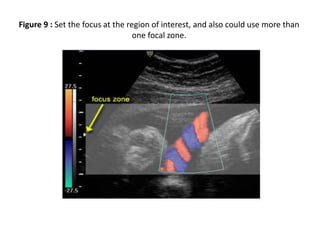

5) Focus: The focus should be at the level of the area of

interest. This can make a significant difference to the

appearance and accuracy of the image

(Figure 9) slides (13/14).

Figure 9 : Set the focus at the region of interest, and also could use more than

one focal zone.